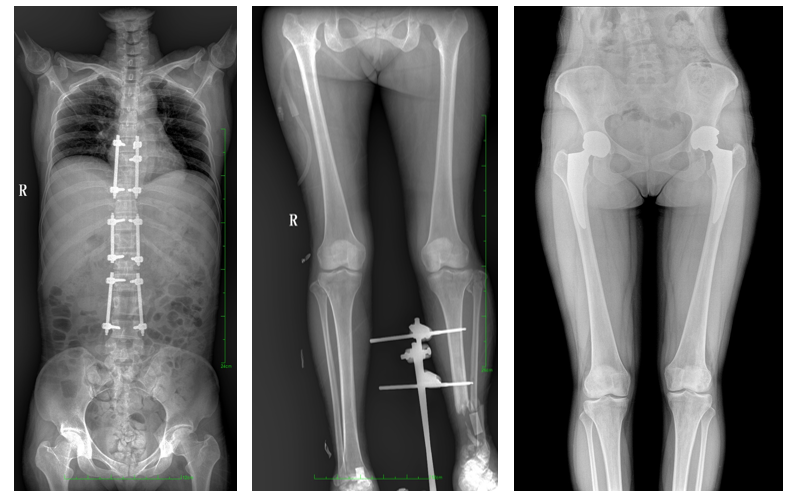

一、成像面積大。17"*34"有效視野,一次成像不拼接。相較于多張攝影再軟件拼接的DR設(shè)備,大視野平板動(dòng)態(tài)DR解決了拼接圖像存在密度不均勻,拼接處圖像配準(zhǔn)和放大效應(yīng)等問題,給臨床帶來了大視野影像解決方案,可一次性覆蓋全脊柱或雙下肢影像。

如:全脊柱狀態(tài)評(píng)估、長(zhǎng)骨關(guān)節(jié)活動(dòng)度、下肢靜脈造影瓣膜功能評(píng)估、消化道功能評(píng)估、脊髓造影等更多大視野臨床應(yīng)用,多面手給醫(yī)生更多驚喜。

PLX8600大視野平板動(dòng)態(tài)DR可在低輻射劑量下獲得患者站立位、臥位的高質(zhì)量影像。搭載自主研發(fā)的圖像均衡處理系統(tǒng),能夠很好的均衡人體不同厚度組織的影像,視野大,圖像清晰,層次豐富。